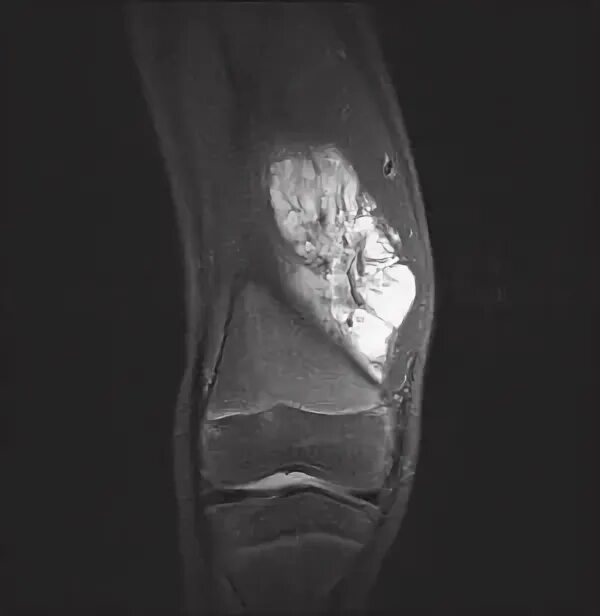

Синовиомы